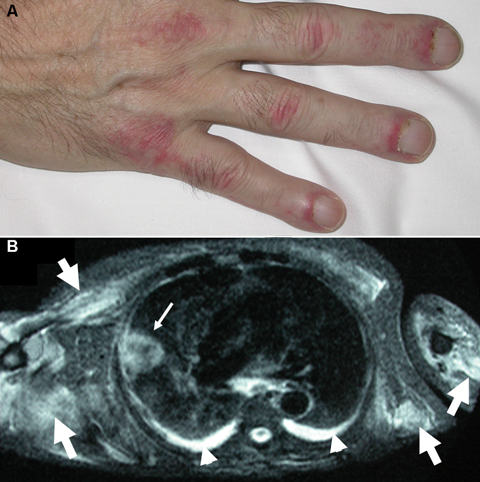

A 64-year-old man was referred for assessment of a symmetric violaceous rash of the dorsal aspect of the fingers (Figure, A), trunk, olecranon processes and malleoli. An oedematous, blue-purple discolouration of the eyelids was also apparent. The patient complained of severe weakness of the proximal muscles and dysphagia. T2-weighted magnetic resonance imaging showed muscular inflammation and a pulmonary mass (Figure, B) that was histologically identified as squamous cell carcinoma and staged as T3 N0 M0.